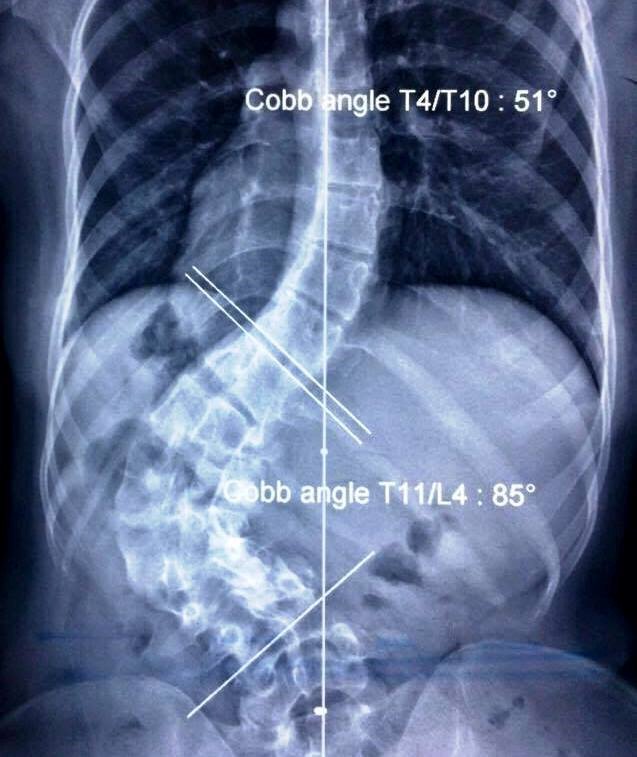

Phụng bị vẹo cột sống từ 85 độ lên 50 độ. Vết sẹo co rút khiến cô gái đau đớn, tưởng chừng phải bỏ học, nhưng đã được nắn chỉnh.

Từ lúc 2 tuổi, Nguyễn Lê Hải Phụng (20 tuổi,Tiền Giang, hiện là sinh viên năm 3 đại học Kinh tế TP.HCM) bị viêm hoại tử, gây sẹo vùng thắt lưng. Sau lần phẫu thuật kéo da ở lưng năm 7 tuổi, sẹo co rút dần, gây ra vẹo cột sống trong quá trình lớn lên. Một năm trở lại đây, biến chứng cột sống khiến cô gái ngồi chỉ được 10 phút thì đau lưng dữ dội, ảnh hưởng nhiều đến sinh hoạt và học tập hàng ngày.

Cột sống bị cong vẹo của cô sinh viên được chụp qua X-quang. (Ảnh: Hoài Nhơn)